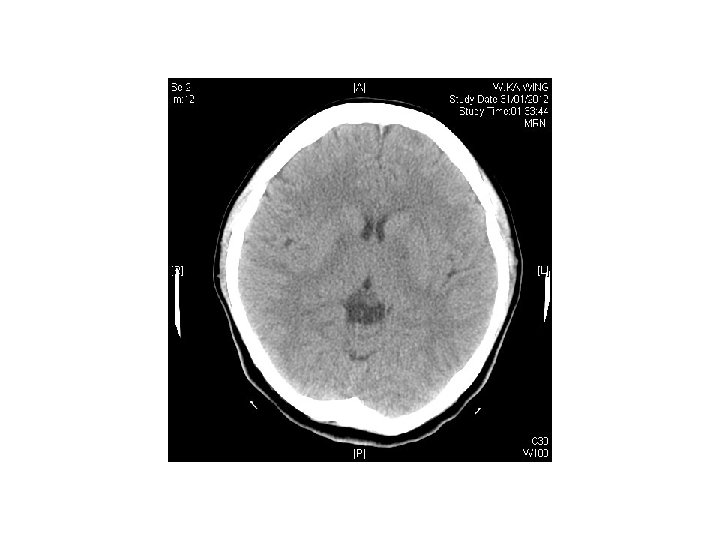

Case 5 • F/25 • She attempted suicide by burning charcoal at home • PE: GCS 14/15, BP 98/73 mm. Hg, Pulse 83/min, Sa. O 2 99% on 100%O 2 • Systems review were unremarkable. No focal neurological sign elicited.

Question • 1) describe the CT findings • 2) what is the diagnosis? • 3) what is the management?

Answers • Symmetrical hypodensity noted at bilateral basal ganglia • Compatible with CO poisoning • Rx : stabilize ABC • Administer 100%O 2 via tight fitting face mask • Intubate and provide IPPV on 100%O 2 if unconscious

• Record ECG, check ABG, COHB level • Consider hyperbaric oxygen therapy if • COHB >25%, pregnant patients with COHB >10%, myocardial ischemia, worsening symptoms despite oxygen therapy, all patients with syncope, neurological or cardiac abnormalities with elevated COHB